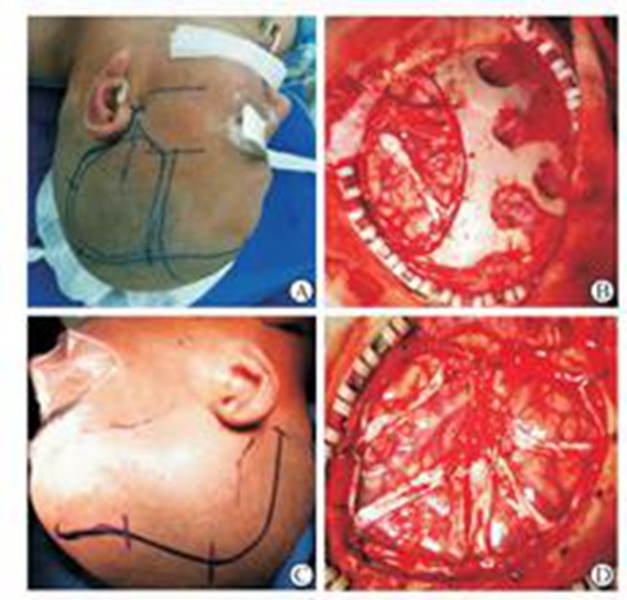

幼兒煙霧病腦手術

幼兒頭部手術煙霧病

煙霧病幼兒頭部

A:煙霧病目前有兩種手術方式,分別是血管搭橋手術和血管貼敷手術。血管搭橋手術是將顳淺動脈進行剝離,然後與大腦中動脈進行吻合搭橋。而血管貼敷手術是將顳淺動脈剝離後貼敷到腦的表面上。通過這兩種手術方式,主要的起到的作用是建立新的側枝循環,從而供應腦……

A:煙霧病的主要手術方式是進行顳淺動脈搭橋手術或者貼敷手術,這種手術是需要進行全身麻醉的,因此做完手術後需要臥床,並且密切觀察病情變化。如果術後恢復順利,那手術後兩三天就可以開始下床活動,早下地能夠起到改善下肢循環的作用,能夠預防出現下肢的深靜……